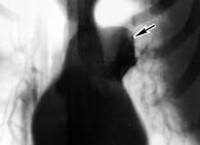

Ведущая роль в диагностике кист средостения принадлежит рентгенологическим исследованиям. Полипозиционная рентгеноскопия и рентгенография грудной клетки, рентгенография пищевода и сердца, пневмомедиастинография позволяют определить локализацию, форму и размеры кисты, ее связь с соседними органами, изменение положения при дыхательных движениях. Для более детальной оценки структуры, толщины стенок кисты, характера содержимого и взаимоотношения с соседними анатомическими образованиями, производится КТ и МРТ средостения.